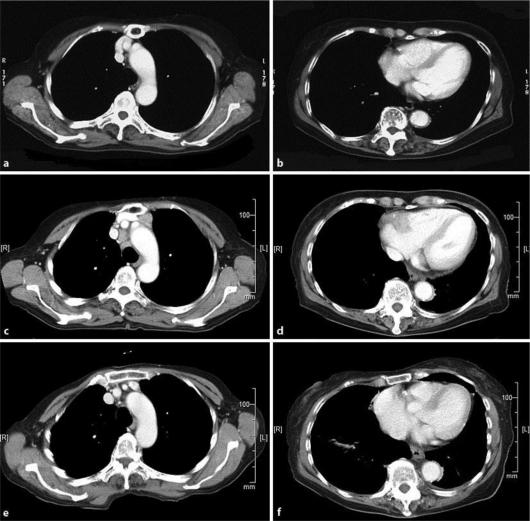

We report a case of facial diffuse large B-cell lymphoma (DLBCL) associated with recurrent metastasis in the heart and other sites in a 76-year-old Japanese woman. Initially, she developed DLBCL in her left upper eyelid that spread into the left orbit (Ann Arbor classification stage I). The lesion went into clinical regression after 4 cycles of rituximab plus cyclophosphamide, doxorubicin, vincristine, and prednisone chemotherapy followed by radiotherapy. More than 3 years later, the lymphoma recurred in her facial skin, together with metastases in the mediastinal lymph nodes and the heart; the tumor in the heart was successfully detected by PET/CT and cardiac MRI. To treat the recurrent lesions, we performed a salvage chemotherapy regimen comprising prednisone, etoposide, procarbazine, and cyclophosphamide, which successfully induced tumor regression.

https://cdn.ncbi.nlm.nih.gov/pmc/blobs/9983/3304513/9df9879c8fd1/cro-0005-0062-g01.jpg